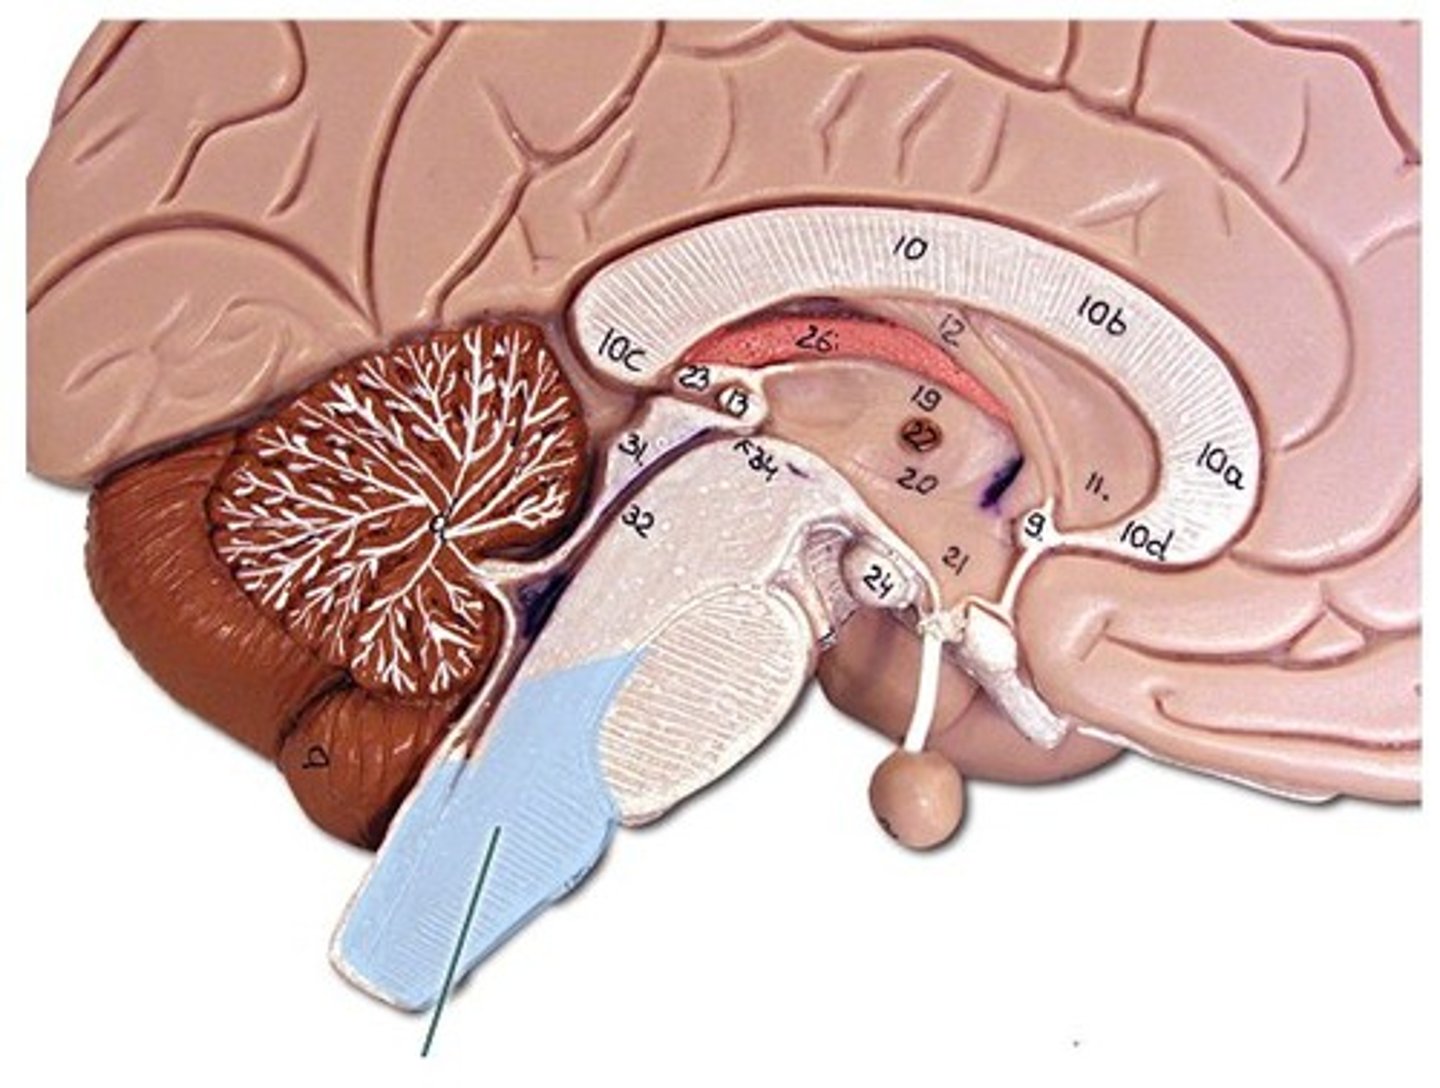

lateral ventricle

A complexly shaped lateral portion of the ventricular system within each hemisphere of the brain.

anterior horn of lateral ventricle

located in the frontal lobe and is the part of the lateral ventricle that lies in front of the interventricular foramen

body of lateral ventricles

located in the parietal lobe, situated between the anterior and posterior horns.

inferior horn of lateral ventricle

located in the temporal lobe of the brain. It is the largest of the three horns and extends from the atrium, curving anteriorly and inferiorly to go under the thalamus and into the temporal lobe

posterior horn of lateral ventricle

located in the occipital lobe of the brain, projecting backward. It is the most posterior part of the C-shaped lateral ventricle and lies deep within the occipital lobe.

interventricular foramen (of monro)

connects lateral ventricles to third ventricle

third ventricle

thin midline space that separates the left and right thalami.

interthalamic adhesion

Connects the two thalami and passes through the third ventricle.

cerebral aqueduct

connects the third and fourth ventricles

fourth ventricle

the ventricle located between the cerebellum and the pons